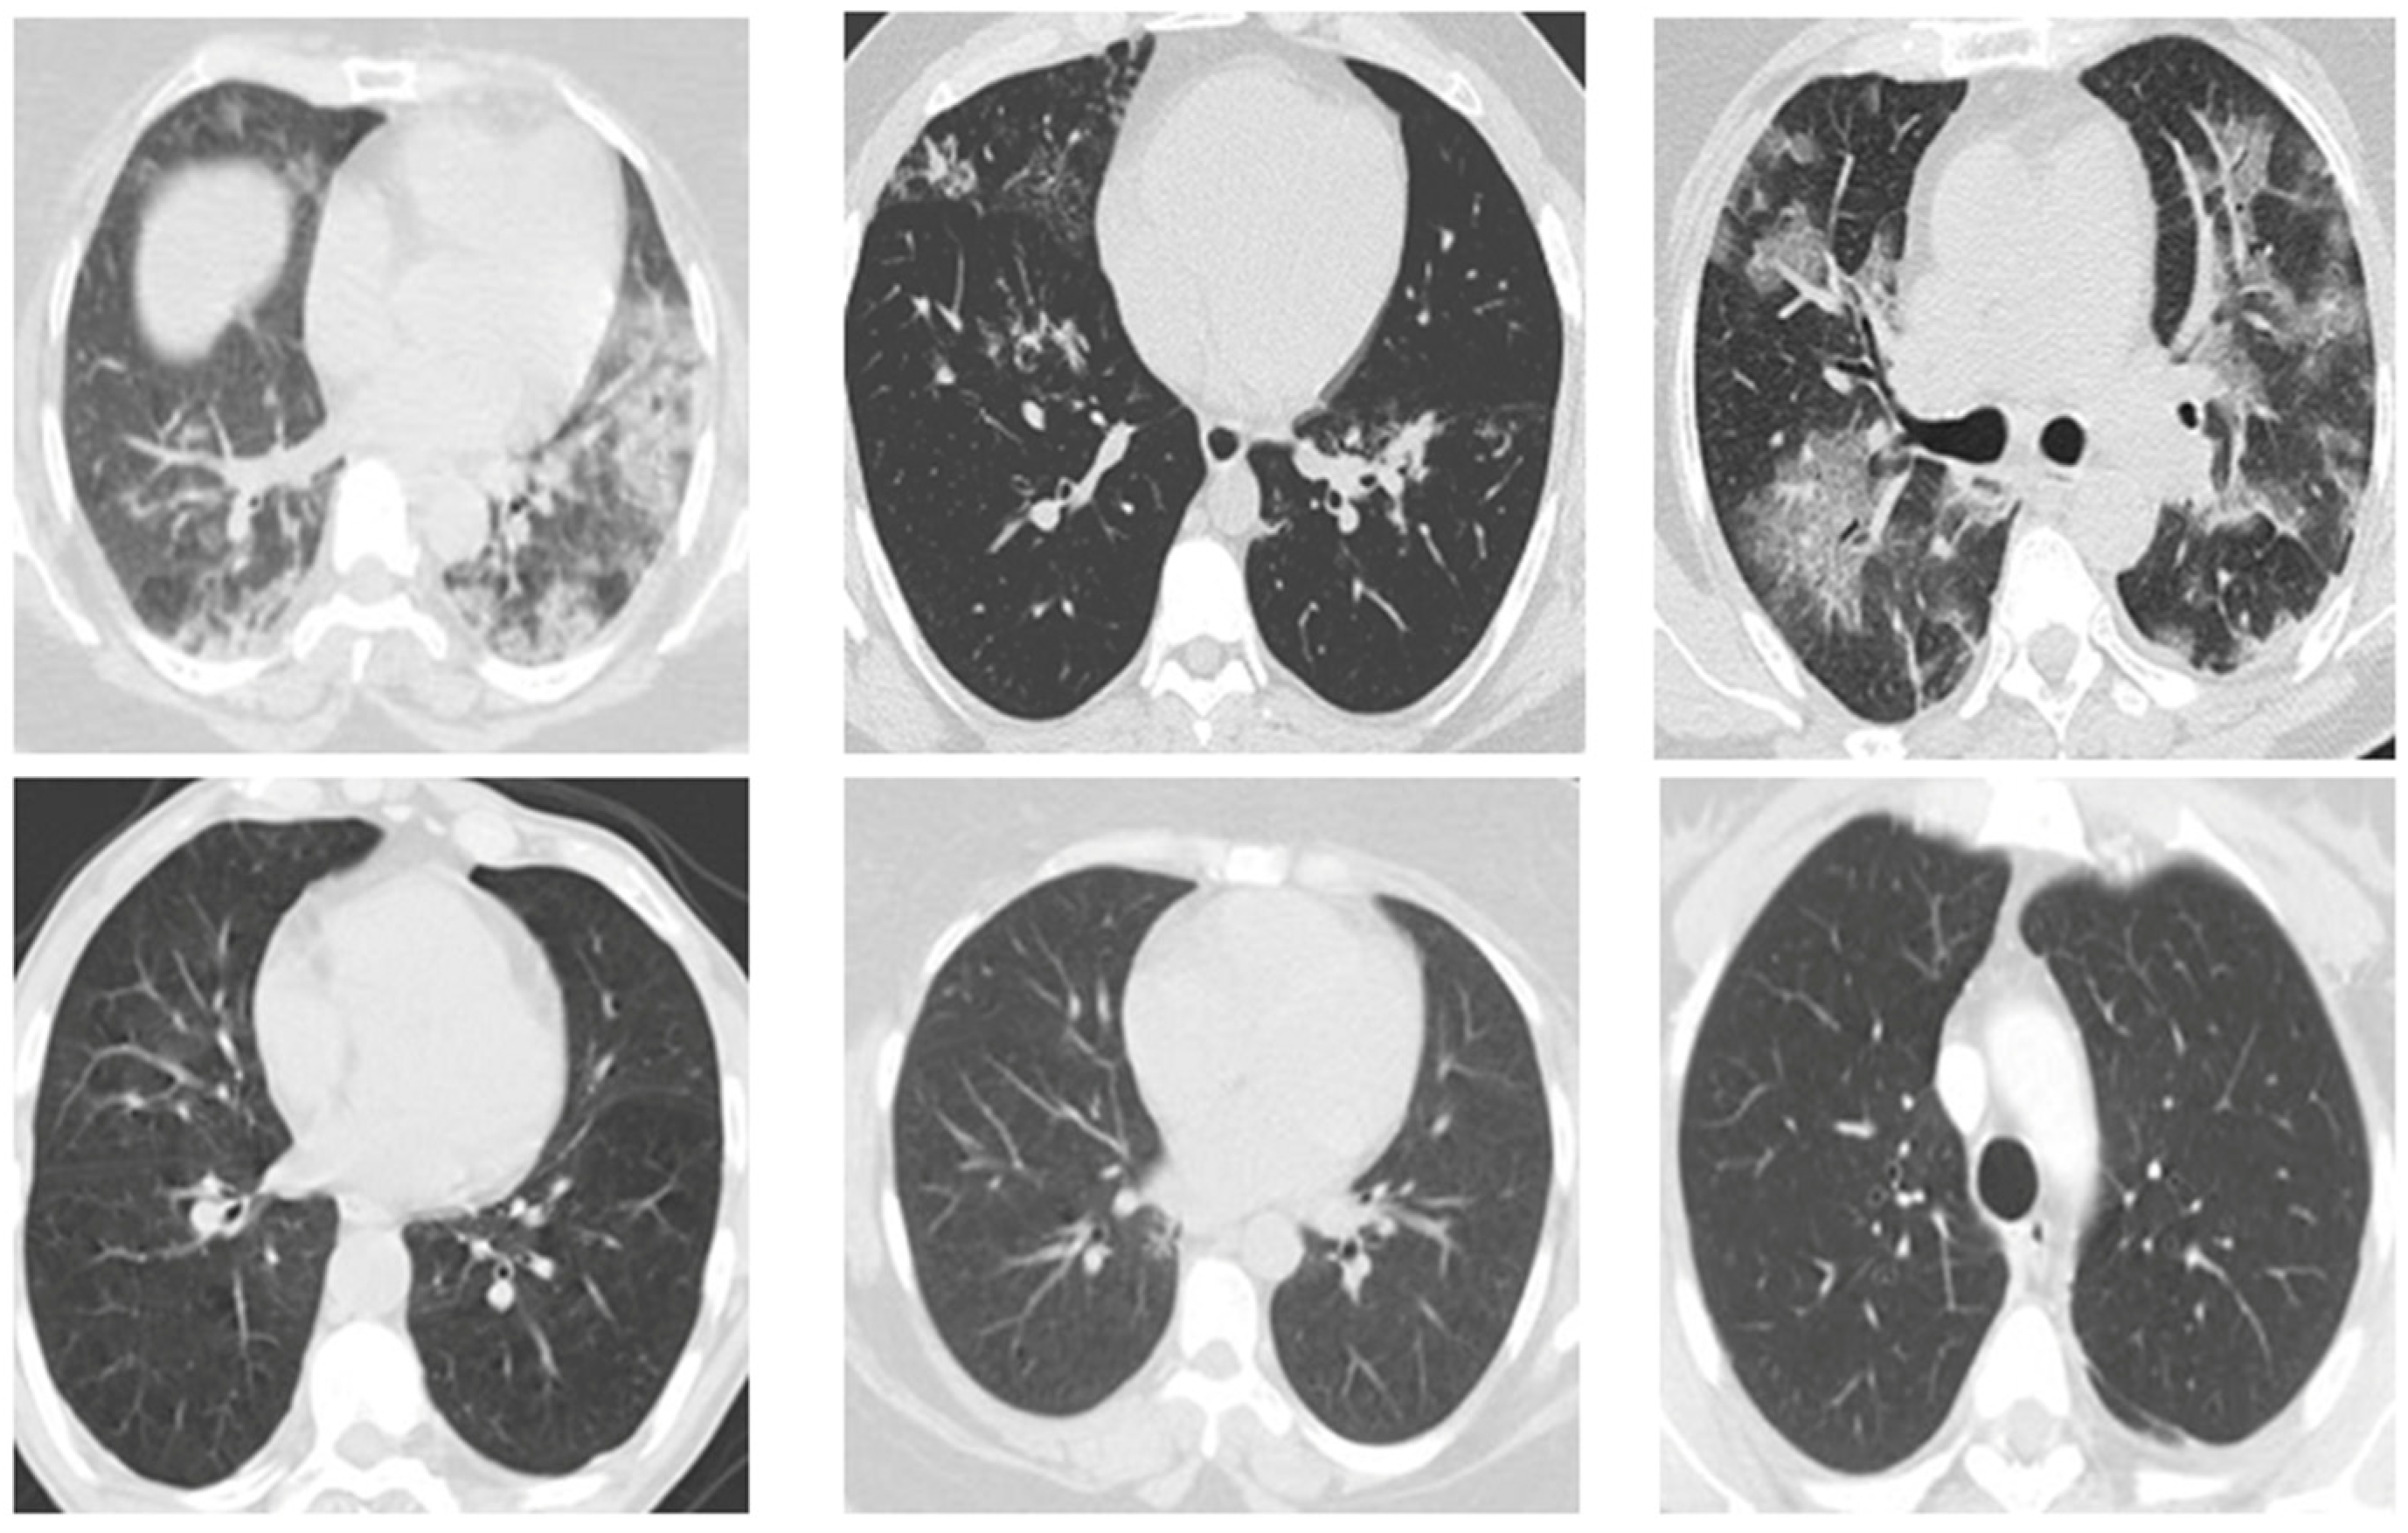

To begin with, every image in the database was resized to 200 × 200 pixels. This is due to the fact that the images in the database are of different sizes, and each image has a different number of pixels. Furthermore, since coronavirus is a lung disease, it is imperative to distinguish lung areas from other body parts. In other regions of the image, white borders can be seen that were derived from the original image using K-means segmentation and morphological methods. The lung image is illustrated in Figure 4, following the application of the pre-processing method.

Figure 4. This figure illustrates the contrast between the image prior to and following the implementation of pre-processing procedures. The raw image of the lung of a person infected with COVID-19 (A); the image of the lung after pre-processing (B).

Fractalfract 08 00237 g004